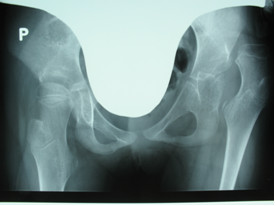

Załączony radiogram przedstawia stawy biodrowe 9 letniego dziecka z mózgowym porażeniem dziecięcym, którego stan funkcjonalny określony został zgodnie z klasyfikacją GMFCS na stopień V. Oceniana w oparciu o przedstawiony radiogram niestabilność stawu biodrowego lewego stanowi wskazanie do: